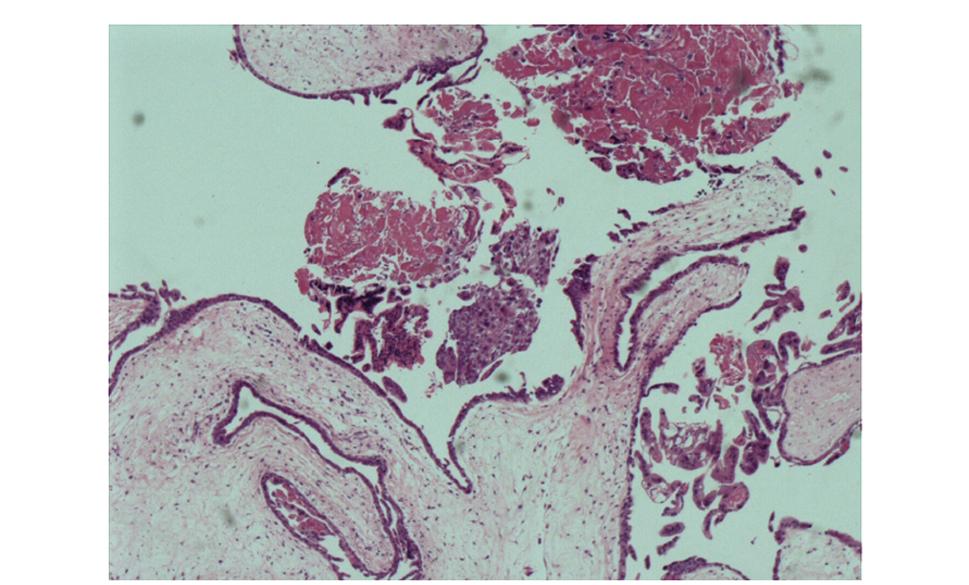

术后病理HE染色后见葡萄胎,滋养细胞中度增生